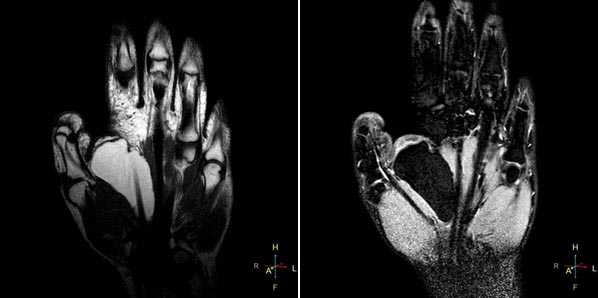

Все виды повреждения кисти можно разделить на несколько групп.

Начнем с МР-диагностики травматических повреждений кисти и лучезапястного сустава.

При клиническом обследовании больных с ушибами лучезапястного сустава и кисти, как правило, определяются болезненность при пальпации, увеличение объема окружающих мягких тканей, а объективно и рентгенологически изменения отсутствуют. Наиболее часто встречаются ушибы метаэпифиза лучевой и локтевой костей, а также полулунной и ладьевидной костей. Ушибы (контузионные поражения) кисти определяются только при МРТ-исследовании, особенно хорошо видно на программах с подавлением сигнала от жира. Морфологически ушиб кости проявляется нарушением целостности трабекул костной ткани с кровоизлиянием и отеком костного мозга. Однако, несмотря на повреждение трабекул костной ткани, рентгенологические исследования, включая КТ, не позволяют обнаружить патологические изменения.

Синдром повреждения сухожилий

Синдром повреждения сухожилий включают частичные и полные их разрывы, проявления теносиновита и посттравматического тендиноза. Основную долю составляют теносиновиты, возникающие изолированно или на фоне повреждения костей и связок. Морфологически теносиновиты характеризуются скоплением синовиальной жидкости под оболочками сухожилия. Рентгенодиагностика в диагностике теносиновитов неинформативна. Наиболее информативны в диагностике теносиновита УЗИ и МРТ.

Теносиновит сухожилий глубокого сгибателя пальцев кисти и длинного сгибателя большого пальца.